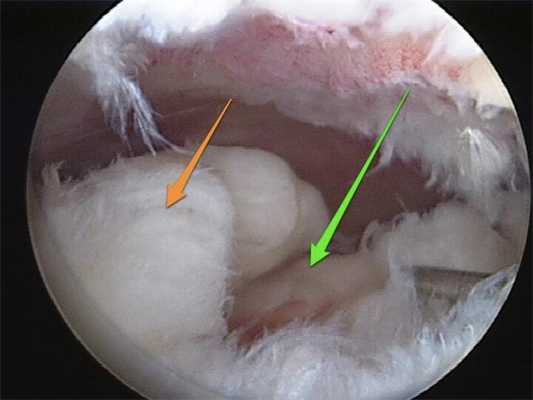

Разволокнение тканей в полости сустава говорит и травматизации.

Еще один пример травмы мениска с видом через артроскоп.